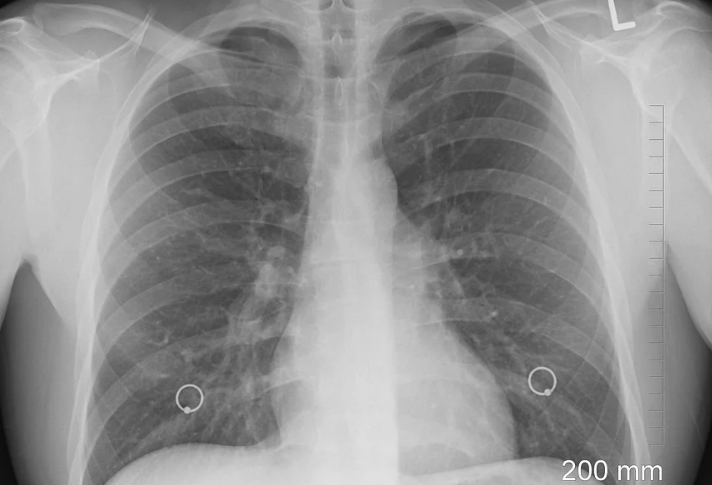

На рентгене видно тень и просветление, так как снимок является негативом пленки . Тень указывает на уплотненные области легких, а белые пятна указывают на скопление воздуха или жидкости .

Фото, как выглядит рак легких на рентгеновском исследовании, для специалистов-онкологов не представляет ничего удивительного, а вот пациенту доставляет мало удовольствия .

Рентген легких здорового человека означает, что при диагностике он не имеет никаких патологий . Как выглядит рентгеновский снимок легкого в норме? Параметры определения .